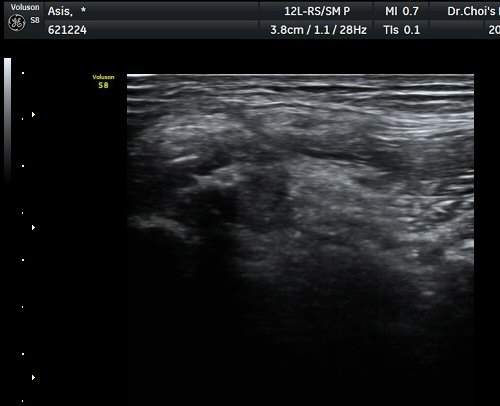

Àü»óÀå°ñ±ØÀÇ ºñ½ºµëÇÑ Á¾´Ü¸é°Ë»ç¿¡¼­ ¼­ÇýºÎ  Àδ밡 ºÎÂøµÇ´Â Àü»óÀå°ñ±ØÀÇ °ß¿­°ñÀýÀÌ

°üÂûµÇ°í(±×¸² 1) ¿ÜÃø´ëÅð±ÙÇǽŰæÀÇ ºÎÁ¾ÀÌ °üÂûµÊ(±×¸² 2, 3). Àü»óÀå°ñ±Ø Ⱦ´Ü¸é°Ë»ç¿¡¼­